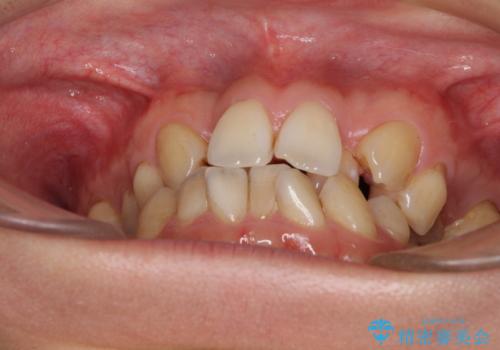

- 前歯の著しいデコボコを気にして来院された患者様です。

上顎の左右側切歯(前から2番目)が裏側に隠れいてる状態で、咬み合わせや清掃性に大きな問題が認められました。

叢生が著しいため、上下左右の小臼歯4本を抜去し、目立たないワイヤー装置にて矯正治療を行うこととしました。

下顎の歯列全体が右側にずれているため、右下のみ第二小臼歯を抜歯し、上顎は補助装置を使用して、極力上下の正中を合う位置にて咬み合わせを改善するようにしました。